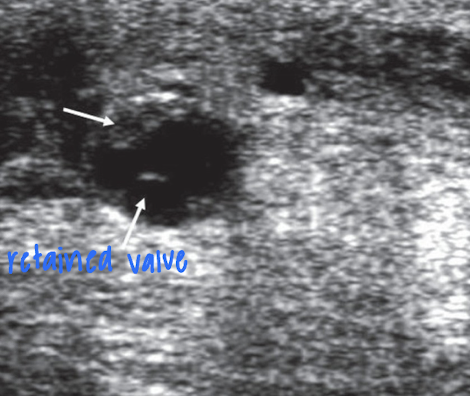

Retained valves

valve remnants that remain due to incomplete valve removal

larger remnants → stenosis

bright echoes